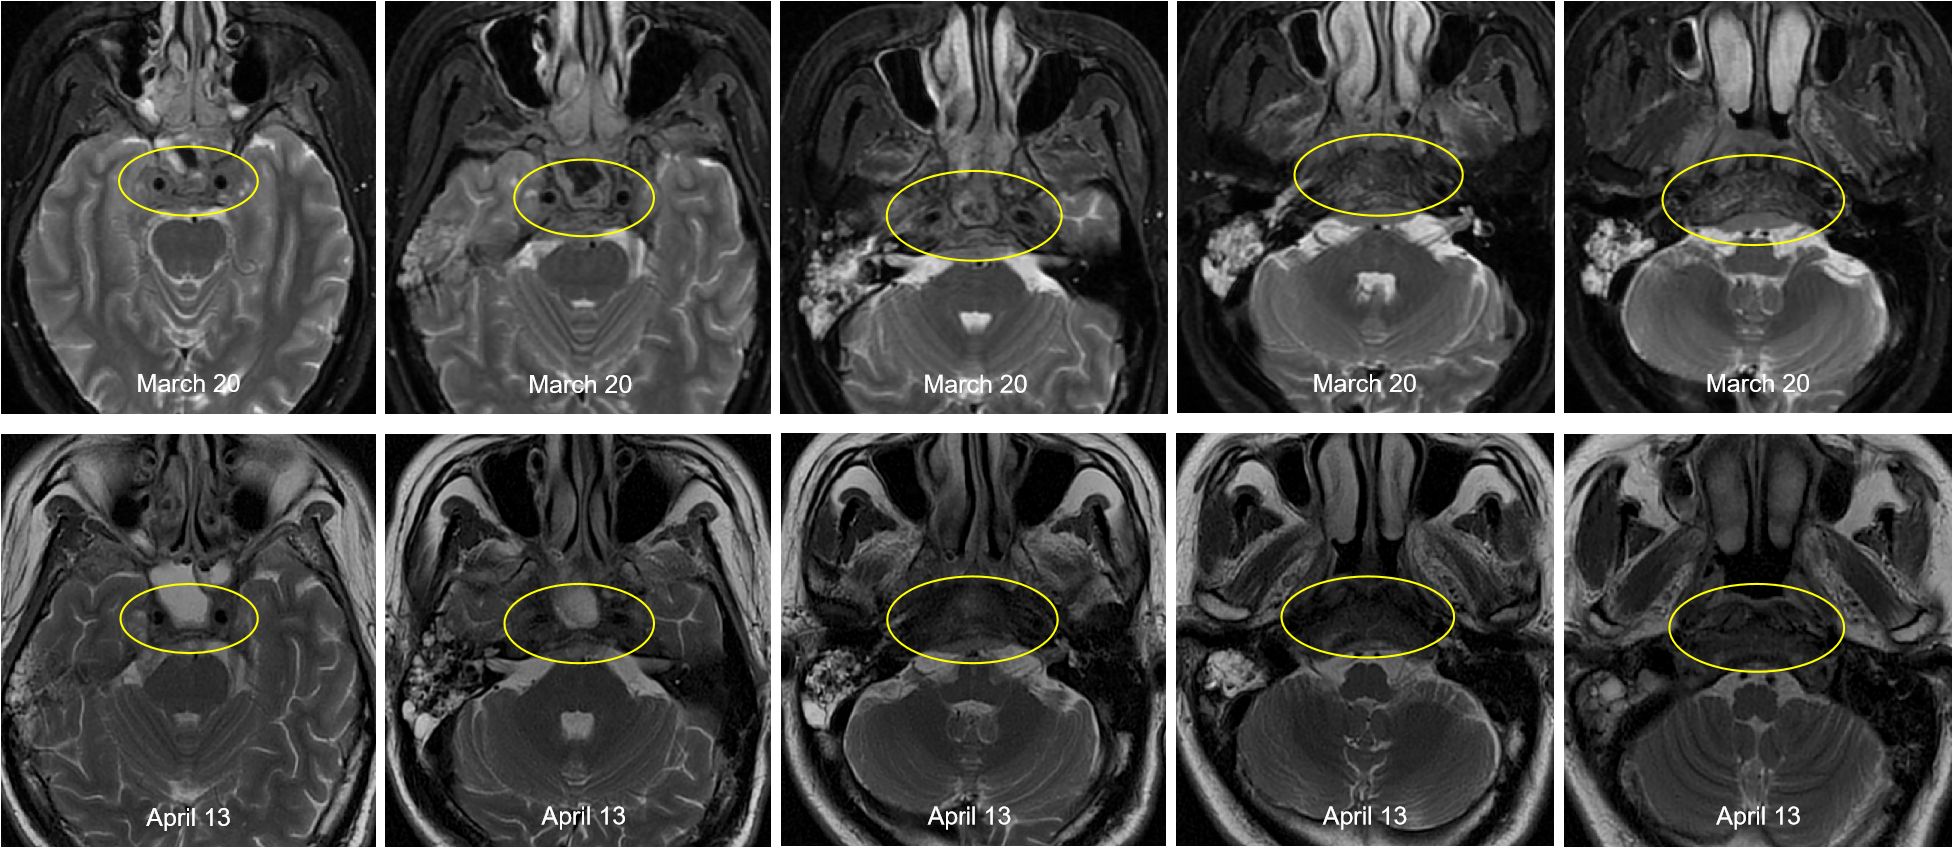

This patient was diagnosed with nasopharyngeal non-keratinizing squamous cell carcinoma (T4N2M1, stage IVB, AJCC 8th), which had indications of palliative chemoimmunotherapy, and we obtained informed consent from patients and families for all of our treatments. Therefore, the planned therapeutic regimen consists of gemcitabine (at a dose of 1 g/m2 on days 1 and 8) and cisplatin (40 mg/m2, days 1-2), plus tislelizumab (200 mg on day 1). Alleviation of reported symptoms was observed following the first dose, potentially reflecting treatment-induced tumor volume reduction and subsequent decreased mass effect on adjacent neural structures. But, on day 3 post-treatment, i.e. on March 29, the patient developed recurrent fever, peaking at 39.2 °C. He also developed severe paroxysmal stabbing pain in the right frontal area suggestive of trigeminal neuralgia, accompanied by increased numbness on the right face. The NRS pain score was 9. His labs were notable for high C-reactive protein (CRP) at 117.46mg/L. His blood culture results (e.g., bacteria and fungi) were negative. The fever is considered to be caused by a bacterial infection (gemcitabine administration on day 8 of the first cycle was withheld due to fever); however, it persisted despite antibiotic therapy, which included cefoperazone and ceftriaxone. After administration of dexamethasone, symptoms were not relieved, and morphine failed to provide adequate analgesic effect. To assess for pulmonary infection and evaluate whether tumor progression is contributing to the clinical deterioration, chest CT and cranial MRI were performed. The CT (April 6) revealed no significant infectious foci (Supplementary Figure 2). The MRI (April 13) demonstrated a slight reduction in tumor size compared to previous imaging (Figure 3).

Figure 3. Comparison of pre- and post-treatment imaging showed a slight reduction in tumor size following chemoimmunotherapy.